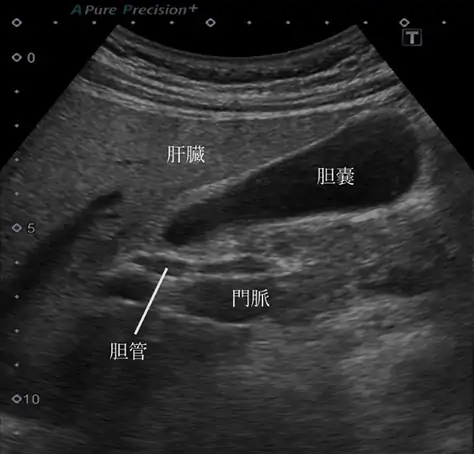

低速の血流を写した超音波検査で見つかった胆のう癌

肝臓、胆のう、膵臓を調べる検査

超音波と CT だけでなく、より専門的な超音波内視鏡、ERCP(内視鏡的逆行性胆管膵管造影)、PTC(経皮経肝胆管造影)、胆道・膵管内視鏡等を行っています。